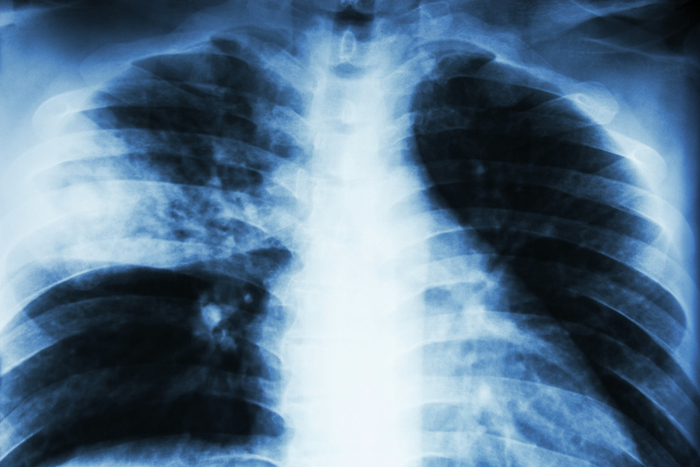

폐렴은 폐(허파)의 세기관지 이하 부위 특히, 폐포(공기주머니)에 발생한 염증이다.

우선 병력 청취와 검진을 통해서 의심할 수 있고, 가슴 x-ray 촬영을 통해 폐음영의 변화를 확인하여 진단할 수 있다. 그러나 x-ray 상 뚜렷한 음영이 확인되지 않는 경우 흉부 전산화 단층촬영(CT) 등의 검사를 실시하기도 한다. 원인이 되는 미생물을 확인하는 것은 쉽지는 않지만 가래를 받아서 원인균을 배양하거나, 혈액배양검사, 소변항원검사 등을 통해서 원인균을 진단할 수도 있다.